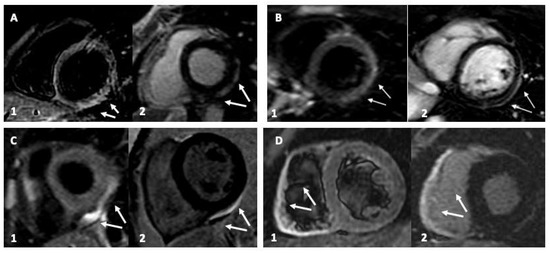

| Patient (n°) | LV EDV 1 | CMR EF 2 | LGE 3 | LGE Distribution | Triple-IR 3 | FU-LGE |

|---|---|---|---|---|---|---|

| 1 | 67 | 55 | y | Pericardium | y | n |

| 2 | 75 | 65 | y | Inferolateral | y | n |

| 3 | 77 | 57 | y | RV | y | n |

| 4 | 62 | 62 | y | Pericardium | y | n |

| 5 | 67 | 60 | y | Inferolateral | y | n |

| 6 | 65 | 67 | y | Inferolateral | y | n |